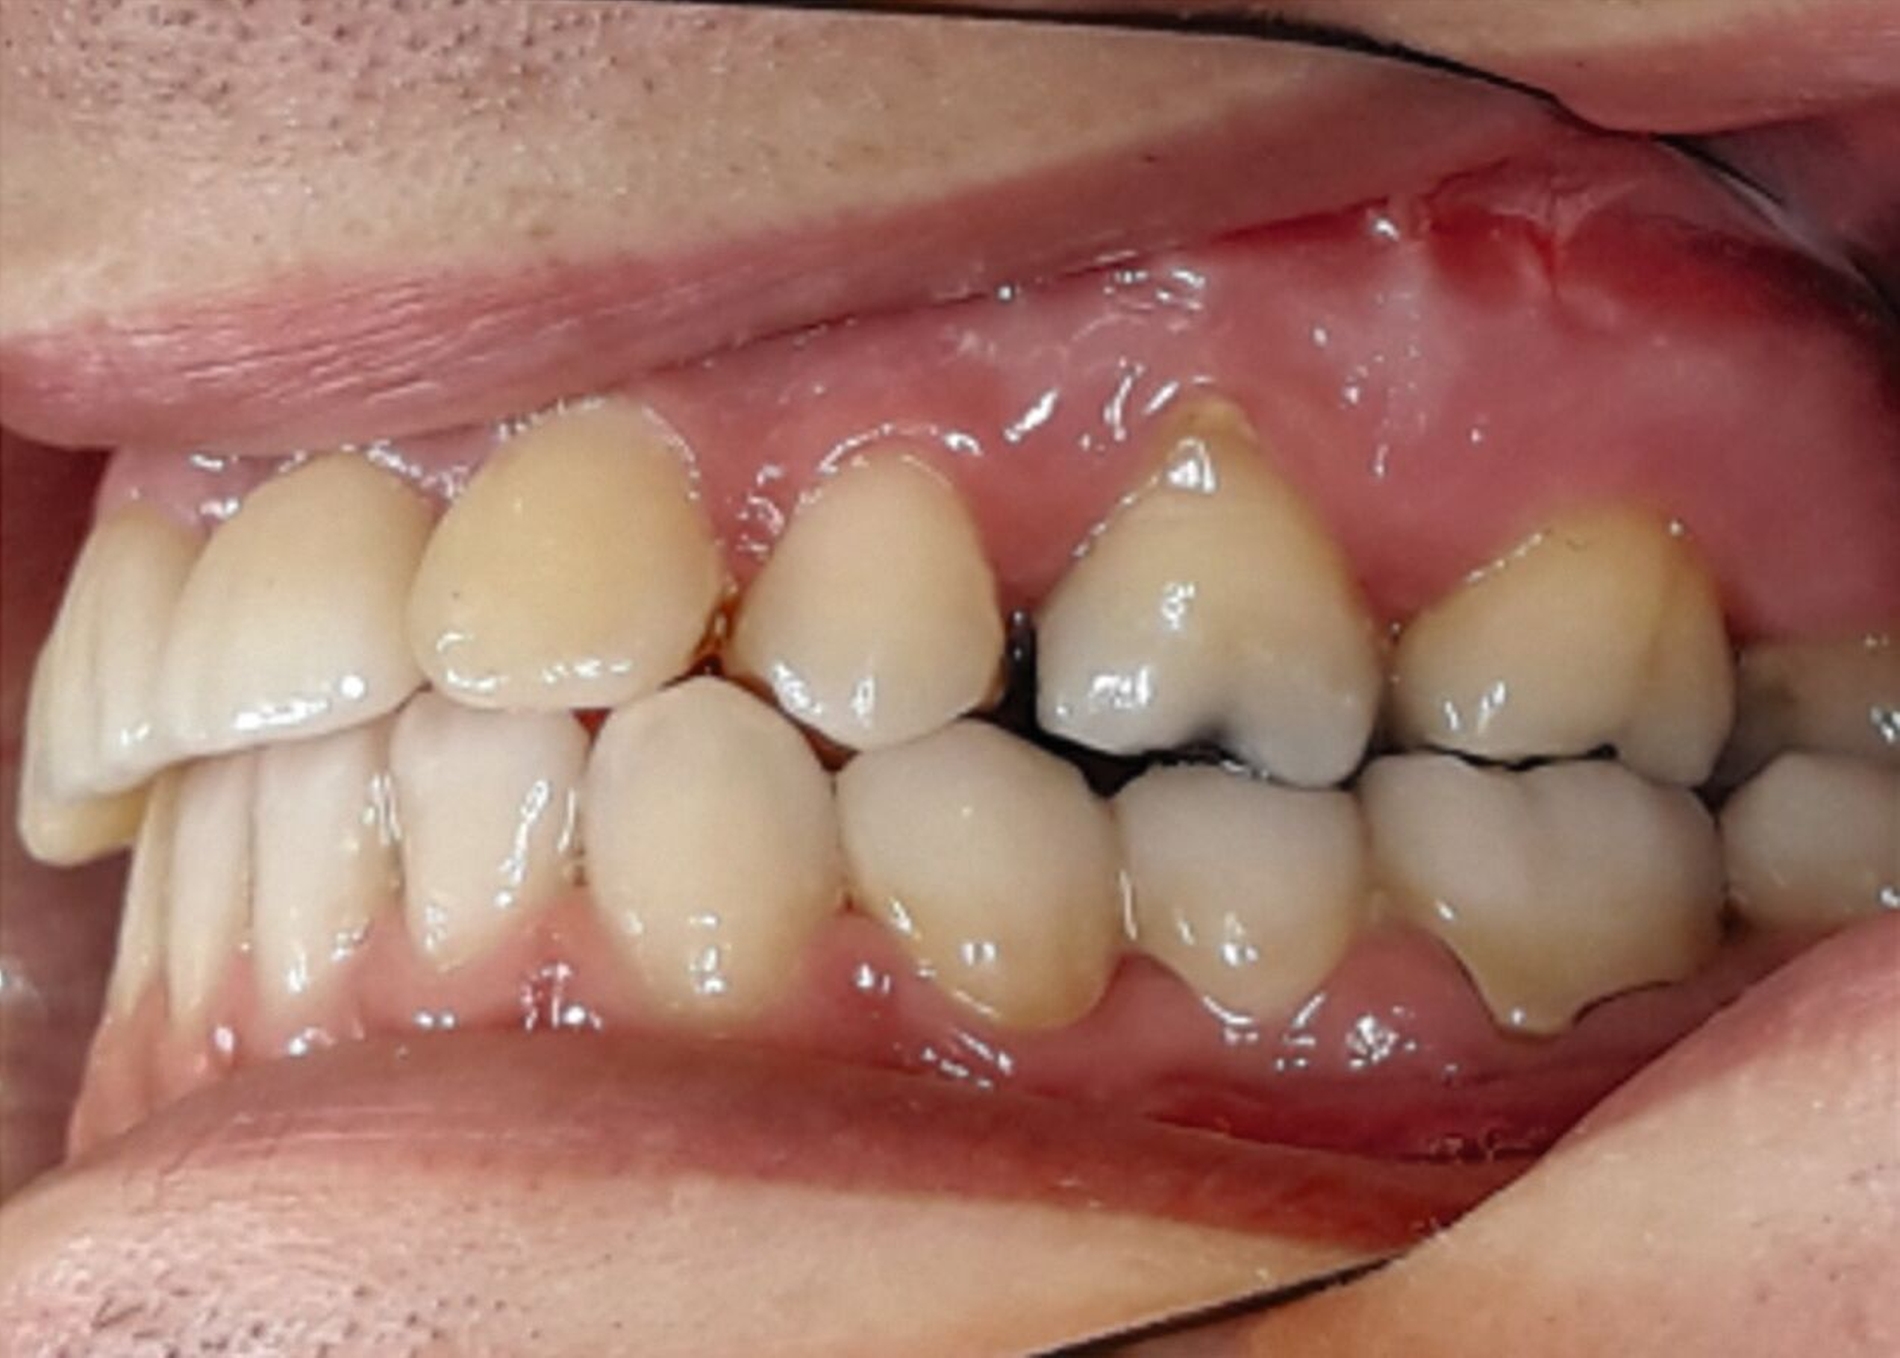

Ein 25-jähriger Patient stellte sich mit dem Wunsch nach Optimierung seines Erscheinungsbildes und seiner Kaufunktion in der kieferorthopädischen Praxis vor (Abbildung 1). Klinisch zeigten sich eine Angle-Klasse-III-Verzahnung mit einer 3/4 Prämolarenbreite Mesialokklusion beidseits und ein zirkulärer Kreuzbiss von 18–12/48–41 und 21–28/31–37. Es lagen ein negativer Overjet von -6,7 mm und ein Overbite von 5,1 mm vor. Eine Mittellinienverschiebung wurde sowohl im Oberkiefer – mit einer Abweichung von 4 mm nach rechts – als auch im Unterkiefer – mit einer Abweichung von 3 mm nach links – diagnostiziert (Abbildungen 2 und 3).